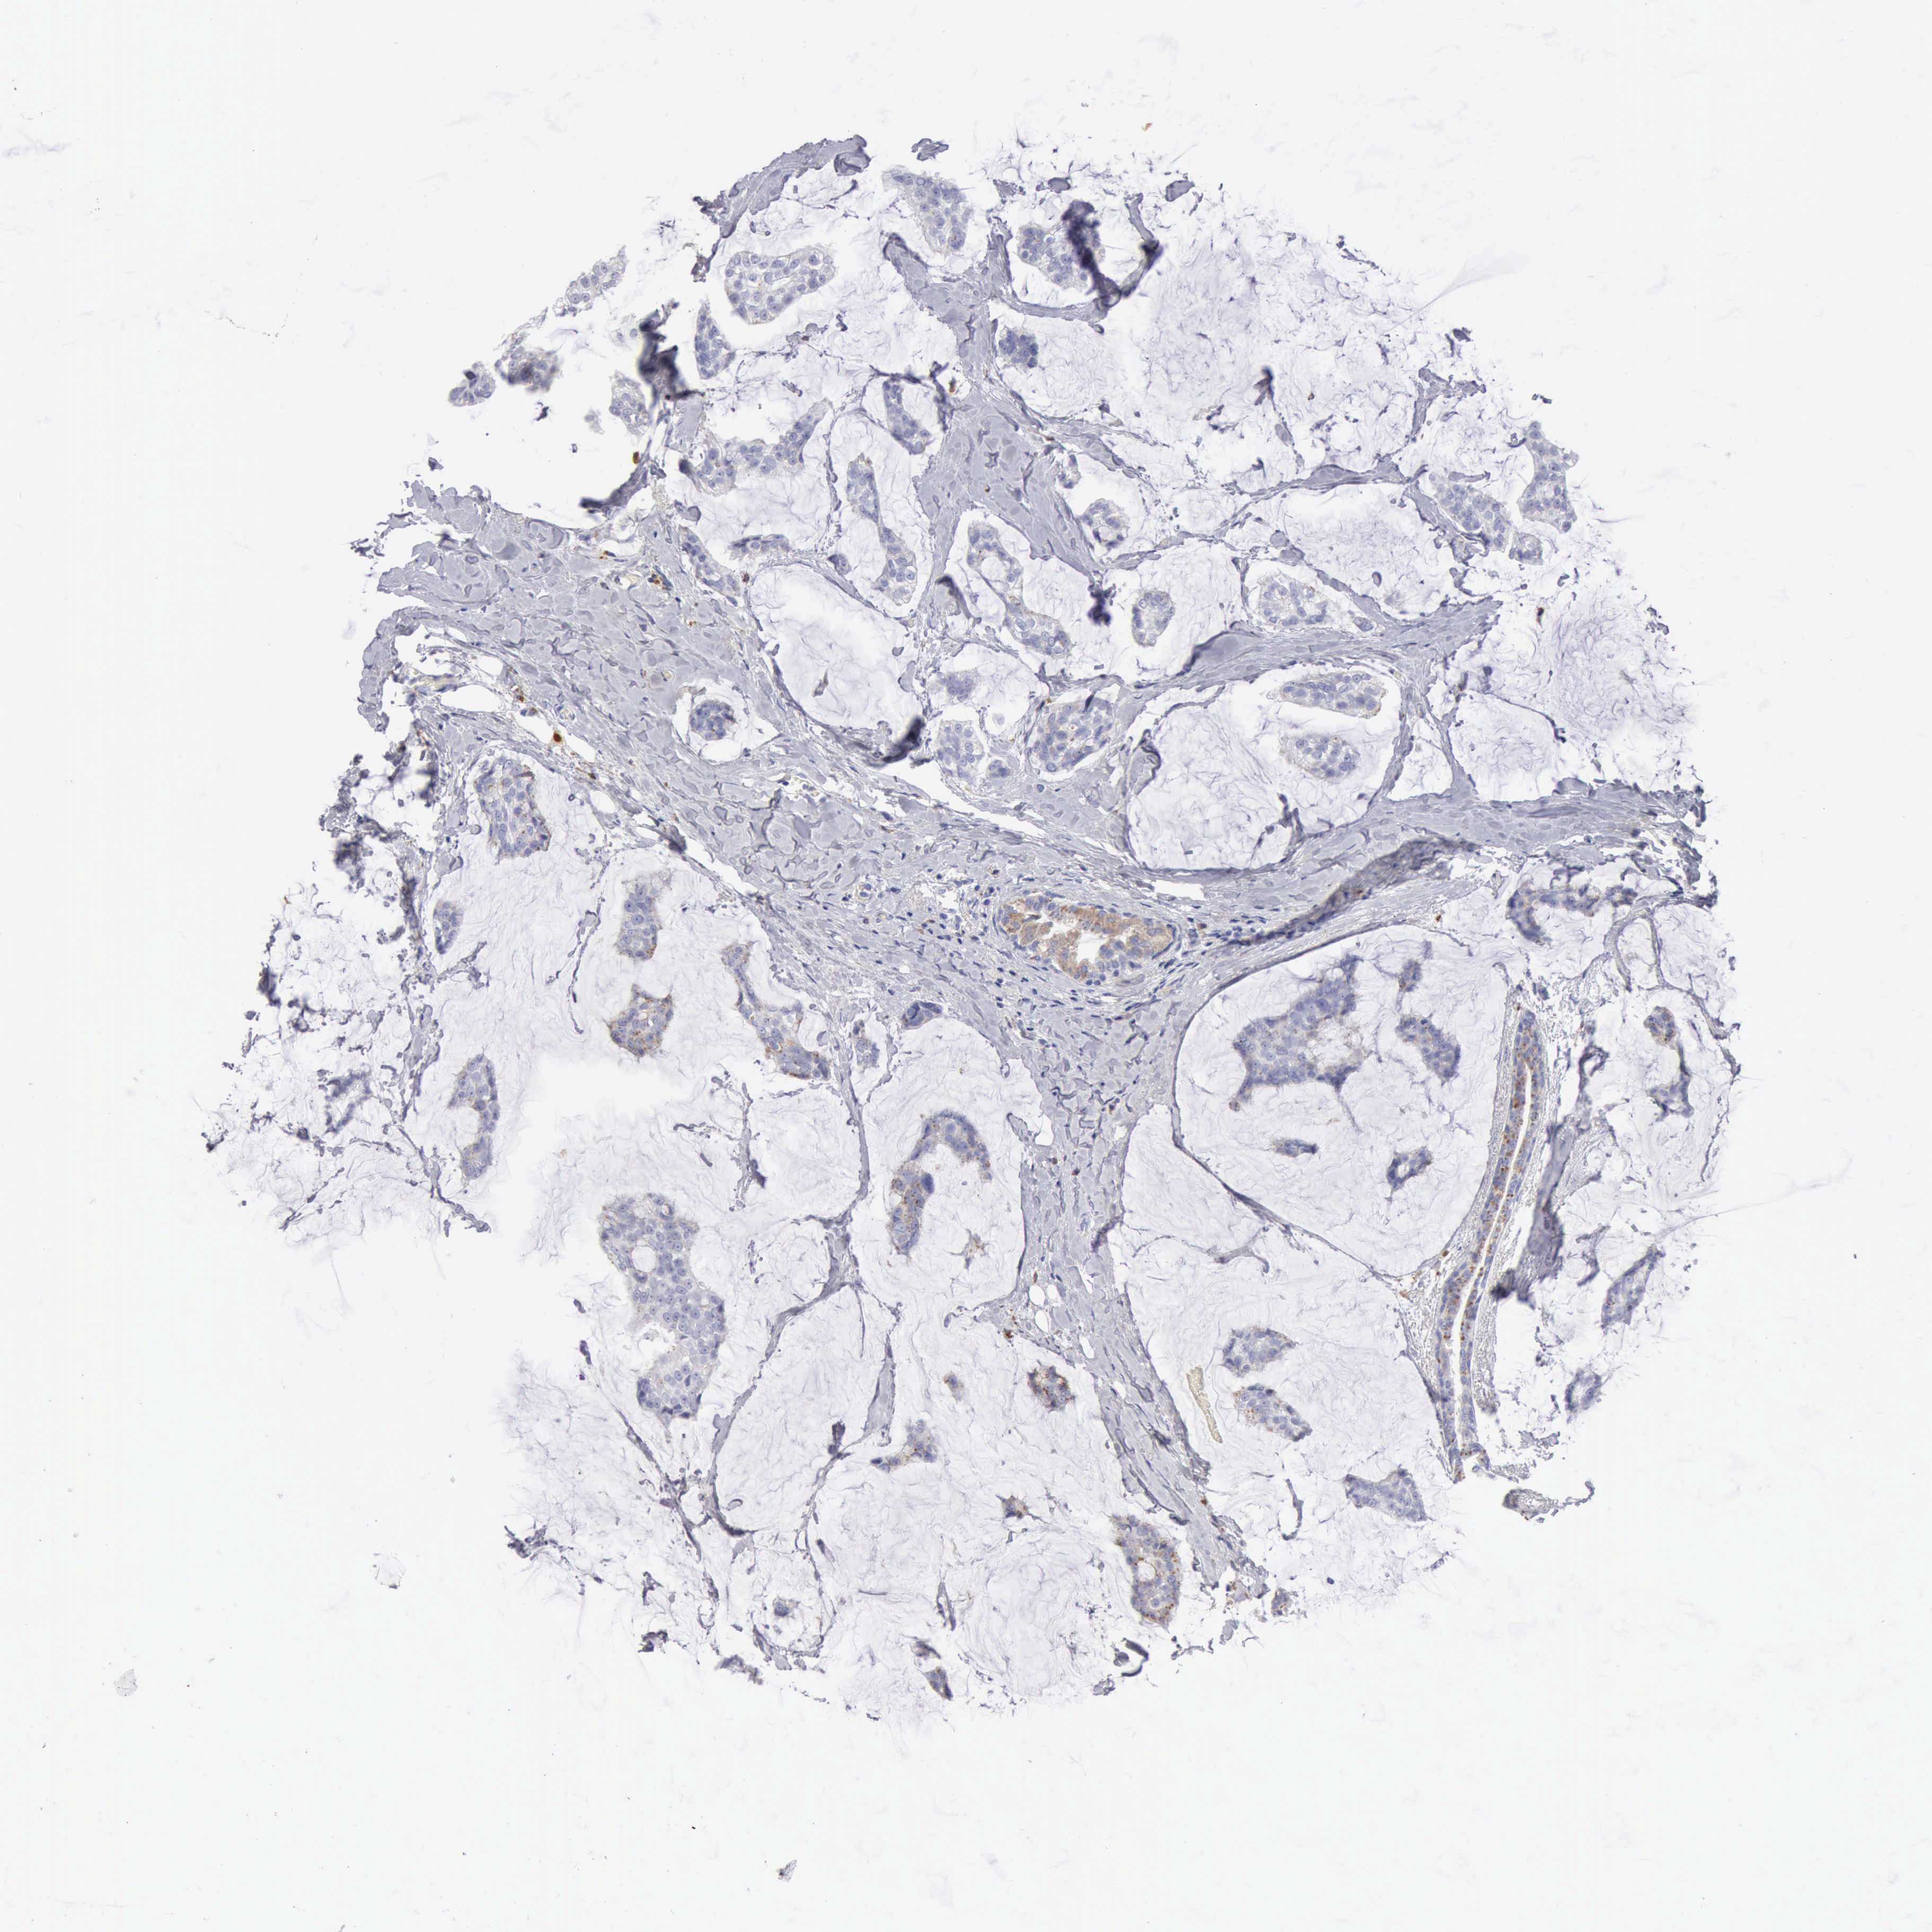

BRCA TCGA BRCA VALIDATION PROTEIN EXPRESSION

ANTIBODIES

AND

VALIDATION